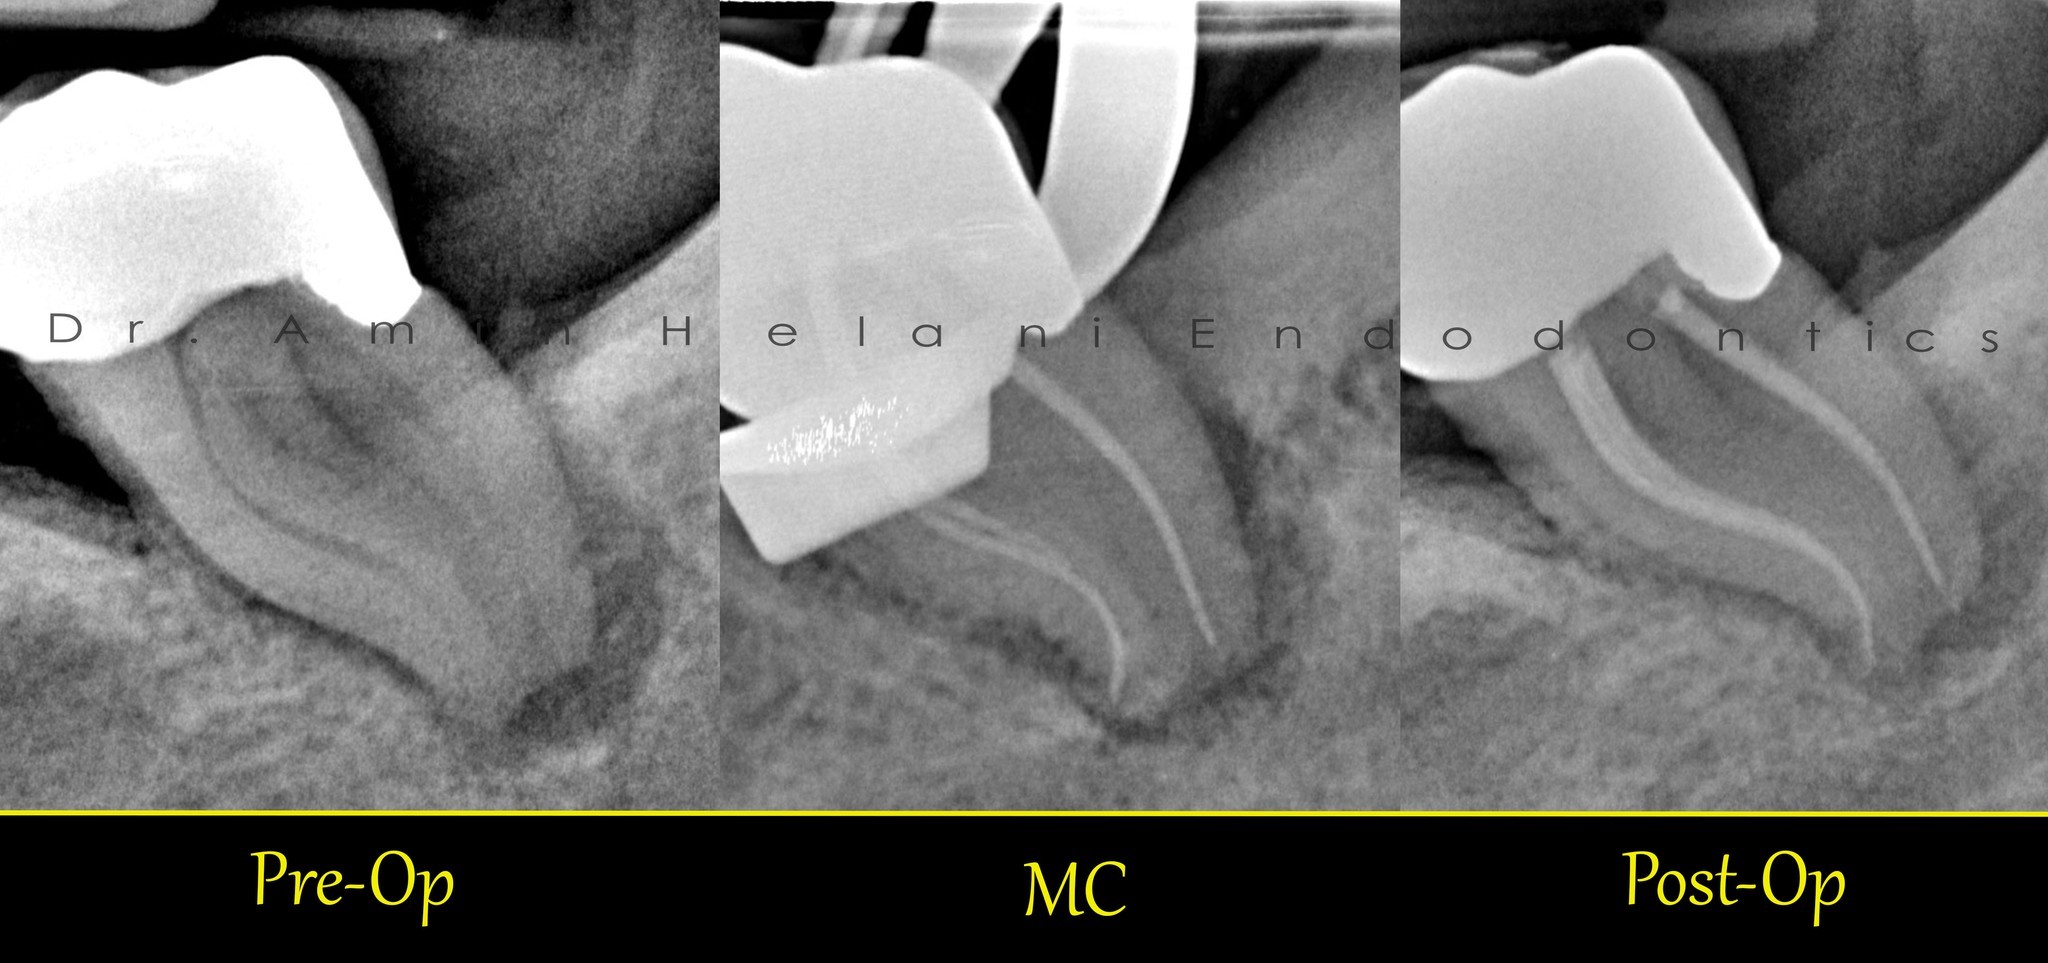

Unterer Molaren mit Mittlerer mesialer Kanal